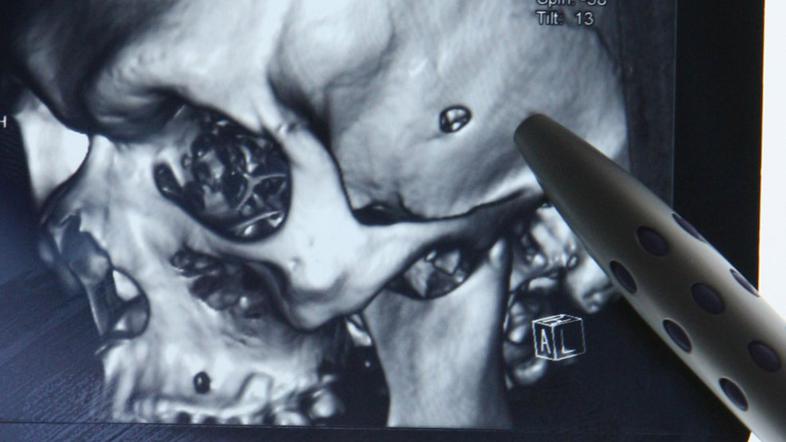

Metek v lobanji Ivo Cagalj/PIXSELL

62-letna Kitajka je preživela, ker se je metek ščasoma obrnil, zlezel v nosno votlino in ni poškodoval možganov.

62-letni Kitajki so z operativnim posegom odstranili metek, ki je bil v njeni glavi kar 48 let, poroča Daily Mail. Po desetih letih neprestanih glavobolov, zamašenega nosu in otečenih limfnih žlez so zdravniki ugotovili, da ima pacientka v glavi 2,5 centimetra dolg in pol centimetra širok metek.

Zdravniki so prepričani, da je preživela le zato, ker se je metek ščasoma obrnil in se zaril v nosno votlino.